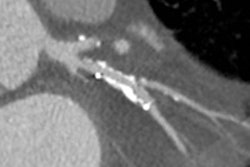

Comparison images demonstrating how high-definition CTA improved reporting accuracy. The case is of a 49-year-old man with previous stent to the circumflex artery with recurrent pain. New scanner technology allows the use of CTCA in patients with known existing heart disease. This is not possible with a conventional CT scanner. This means the interventional cardiologist has all the required information to plan the subsequent intervention. Top left image shows a stent in the circumflex artery but no stenosis. Bottom left shows an occluded right coronary. Top middle also is of the circumflex but demonstrates how the use of the Discovery CT750 HD scanner (GE Healthcare) allows clear visualization of the short stenosis, despite the stent and high level of calcium in the arteries. Top right is a conventional left coronary angiogram confirming the CT findings. Bottom right is the right coronary angiogram confirming findings. All images courtesy of Dr. Carl Roobottom.Having conducted an audit of their service for rate and cause of nondiagnosis in 2009, the Plymouth researchers decided to carry out a reaudit. All attendees for coronary CTA (CCTA) examinations for the investigation of coronary artery disease during a three-month period were reviewed. The analysis included 329 patients, and the cohort was similar to the original one, although it was older (59 versus 61 years) and with higher body mass indices.